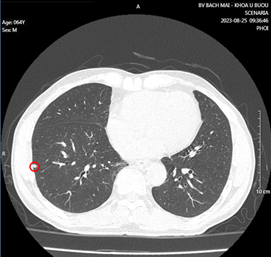

Hình 2: Vài nốt đặc nhu mô phổi 2 bên, kích thước lớn nhất 5x6mm